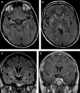

Mesial temporal sclerosis

Hippocampal sclerosis (HS) is a neuropathological condition with severe neuronal cell loss and gliosis in the hippocampus, specifically in the CA-1 (Cornu Ammonis area 1) and subiculum of the hippocampus. It was first described in 1880 by Wilhelm Sommer. [Source: Wikipedia ]